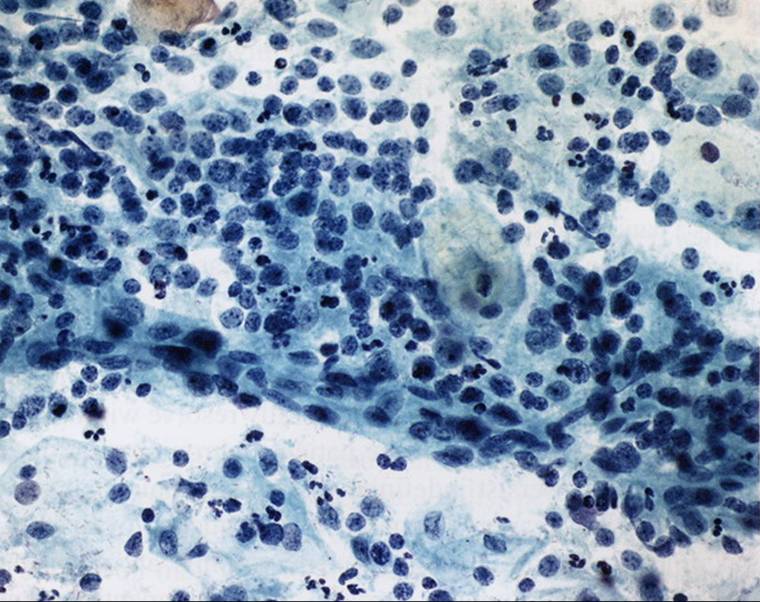

TBS-25淋巴细胞性宫颈炎